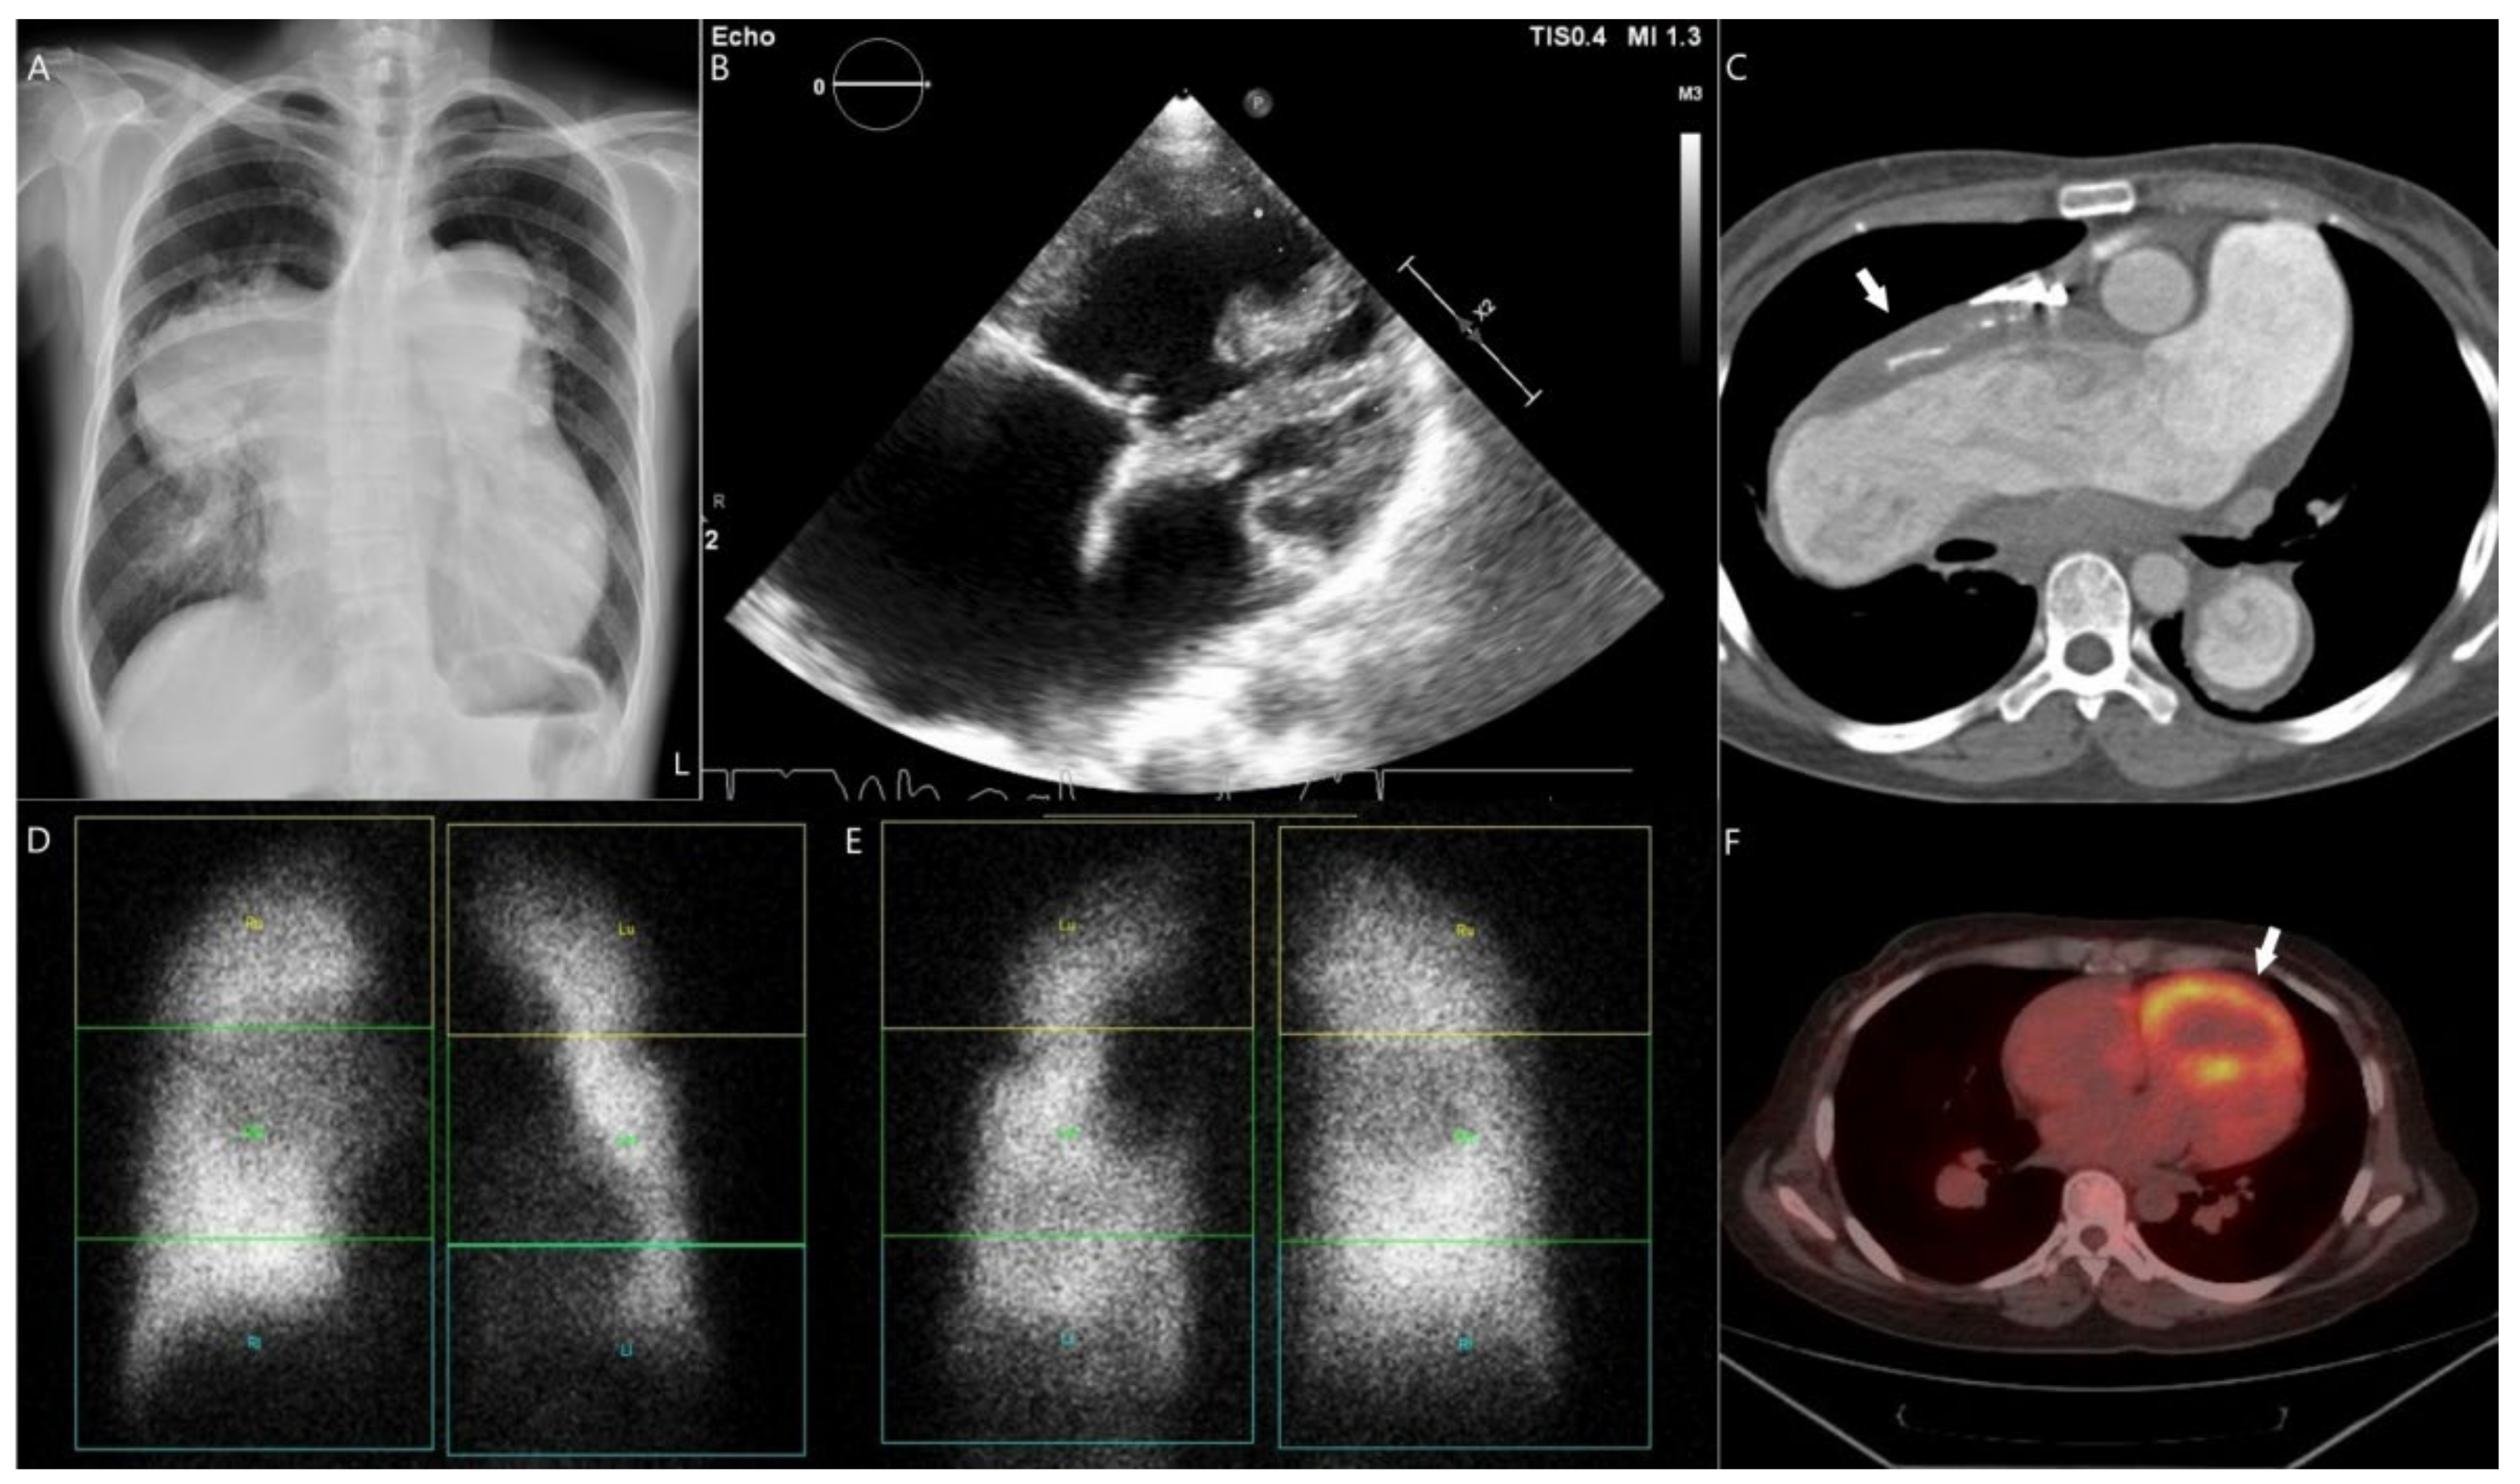

3.1. Case 1

3.2. Case 2

3.3. Case 3

3.4. Case 4

3.5. Case 5